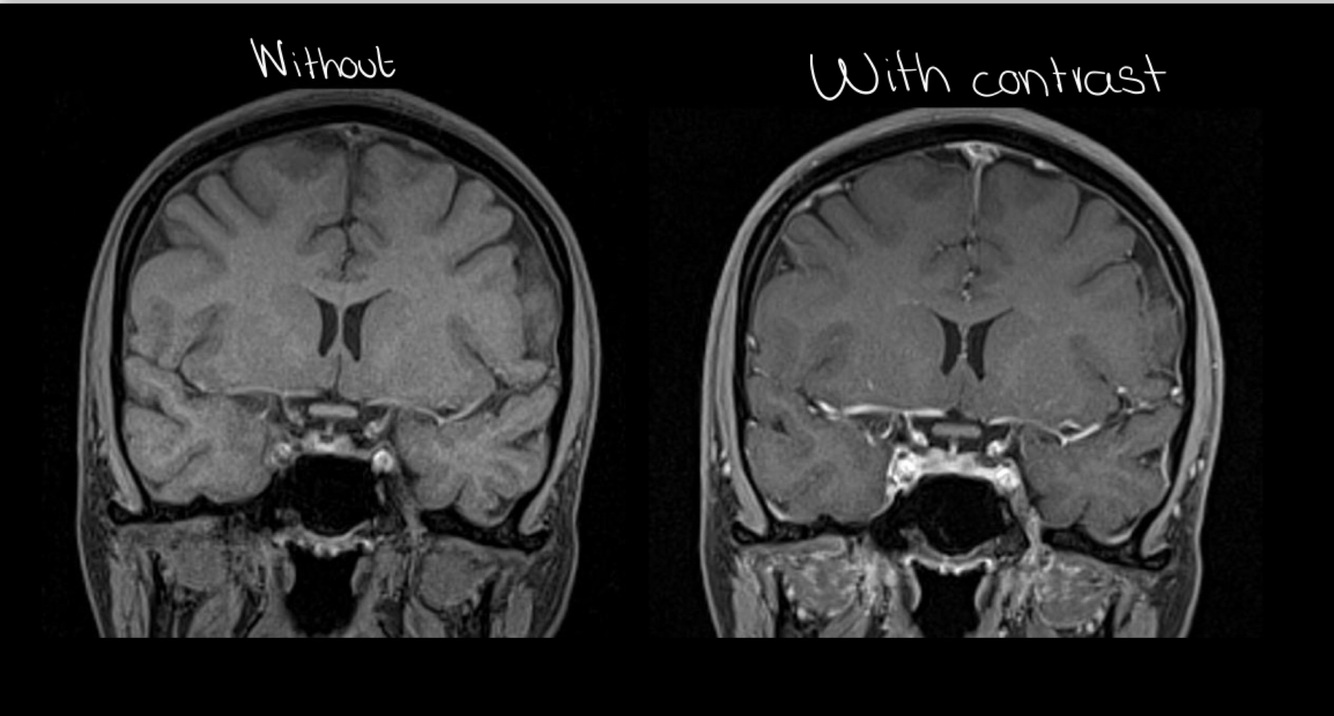

Normally, we use contrast in the brain (T/F)

FALSE: it stays the same after contrast